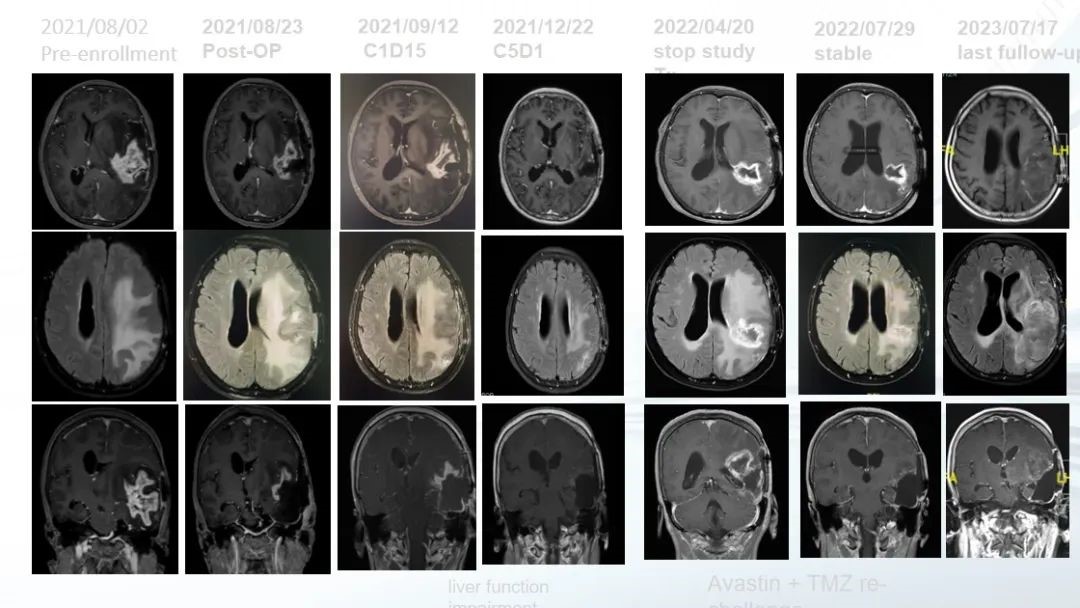

患者,女,59岁。

2020年12月14日

首次手术病理证实为GBM(IDH 野生型,TERT突变),放疗同步替莫唑胺(TMZ)加后续化疗5个月后复发。

2021年8月

入组本研究治疗,术前给予卡瑞利珠单抗及阿帕替尼;2021年8月18日再次手术,证实为复发。后续7个周期(7个月)研究性治疗,肿瘤CR。后因出现肝功能异常退出研究性治疗。

2022年改为贝伐珠单抗加TMZ小剂量方案。至2023年7月(末次随访)肿瘤稳定。患者自首次诊断生存已51个月,入组本研究治疗后生存已24个月。

图.病例的影像资料